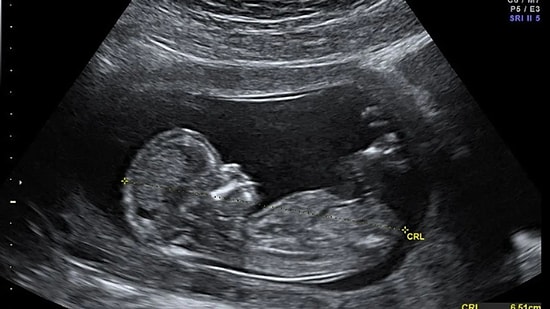

Gebelik Kesesi Nedir? Gebelik Kesesi Ne Zaman Görülür?

Hamilelik testi pozitif çıktıktan sonra ve kanda HCG seviyelerini ölçen test hamileliği doğruladıktan sonra, hamileliğin oluşumu ile ilgili bir sonraki kanıt ultrasondur. Ultrasonografide rahim içinde yerleşmiş bir gebelik kesesinin gözlenmesi ile gebelik tanısı kesinleşir. Peki, gebelik kesesi nedir? Gebelik kesesi ne zaman görülür? Bilinmesi gerekenleri haberimizde sizler için derledik...